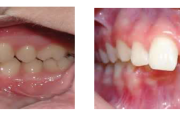

Normaalse jäävhammaskonna pilt küljelt ja eest vaadatuna.

Ruumipuudus eesmiste hammaste osas